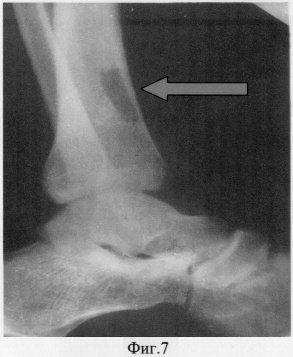

Вторым этапом для ликвидации кожно-костного дефекта согласно предлагаемому способу выделен передний большеберцовый сосудистый пучок с уровня голеностопного сустава до метафизарной части дистального отдела большеберцовой кости, где и был взят костный фрагмент размерами 3×1×1 сантиметр вместе с кожно-фасциальным тыльным лоскутом стопы размерами 5×3 сантиметра (фиг.6, 7).

Большеберцовый сосудистый пучок пересечен в проксимальной своей части. Сформированный комплекс тканей на дистальной сосудистой ножке ротирован на 180 градусов и перемещен на передний отдел стопы в зону поражения 1-го пальца.